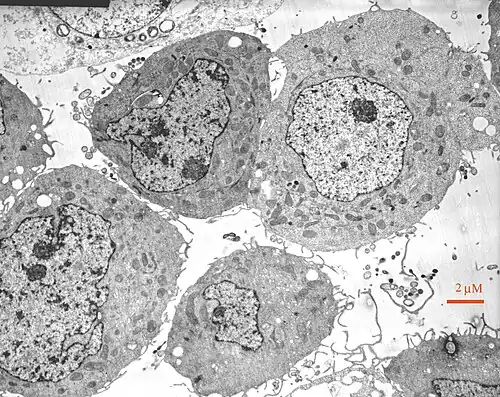

3. Electron Microscopy

The third method is electron microscopy, which uses uses an electron microscope that conducts an electron ray. The electron beams are aimed at the macromolecules and then impose an image of the molecule and its structure upon fluorescent or photographic film for us to see. Sometimes they are even sent directly to a screen, such as a computer screen. This image is a black a white picture but is still very useful in determining structure.